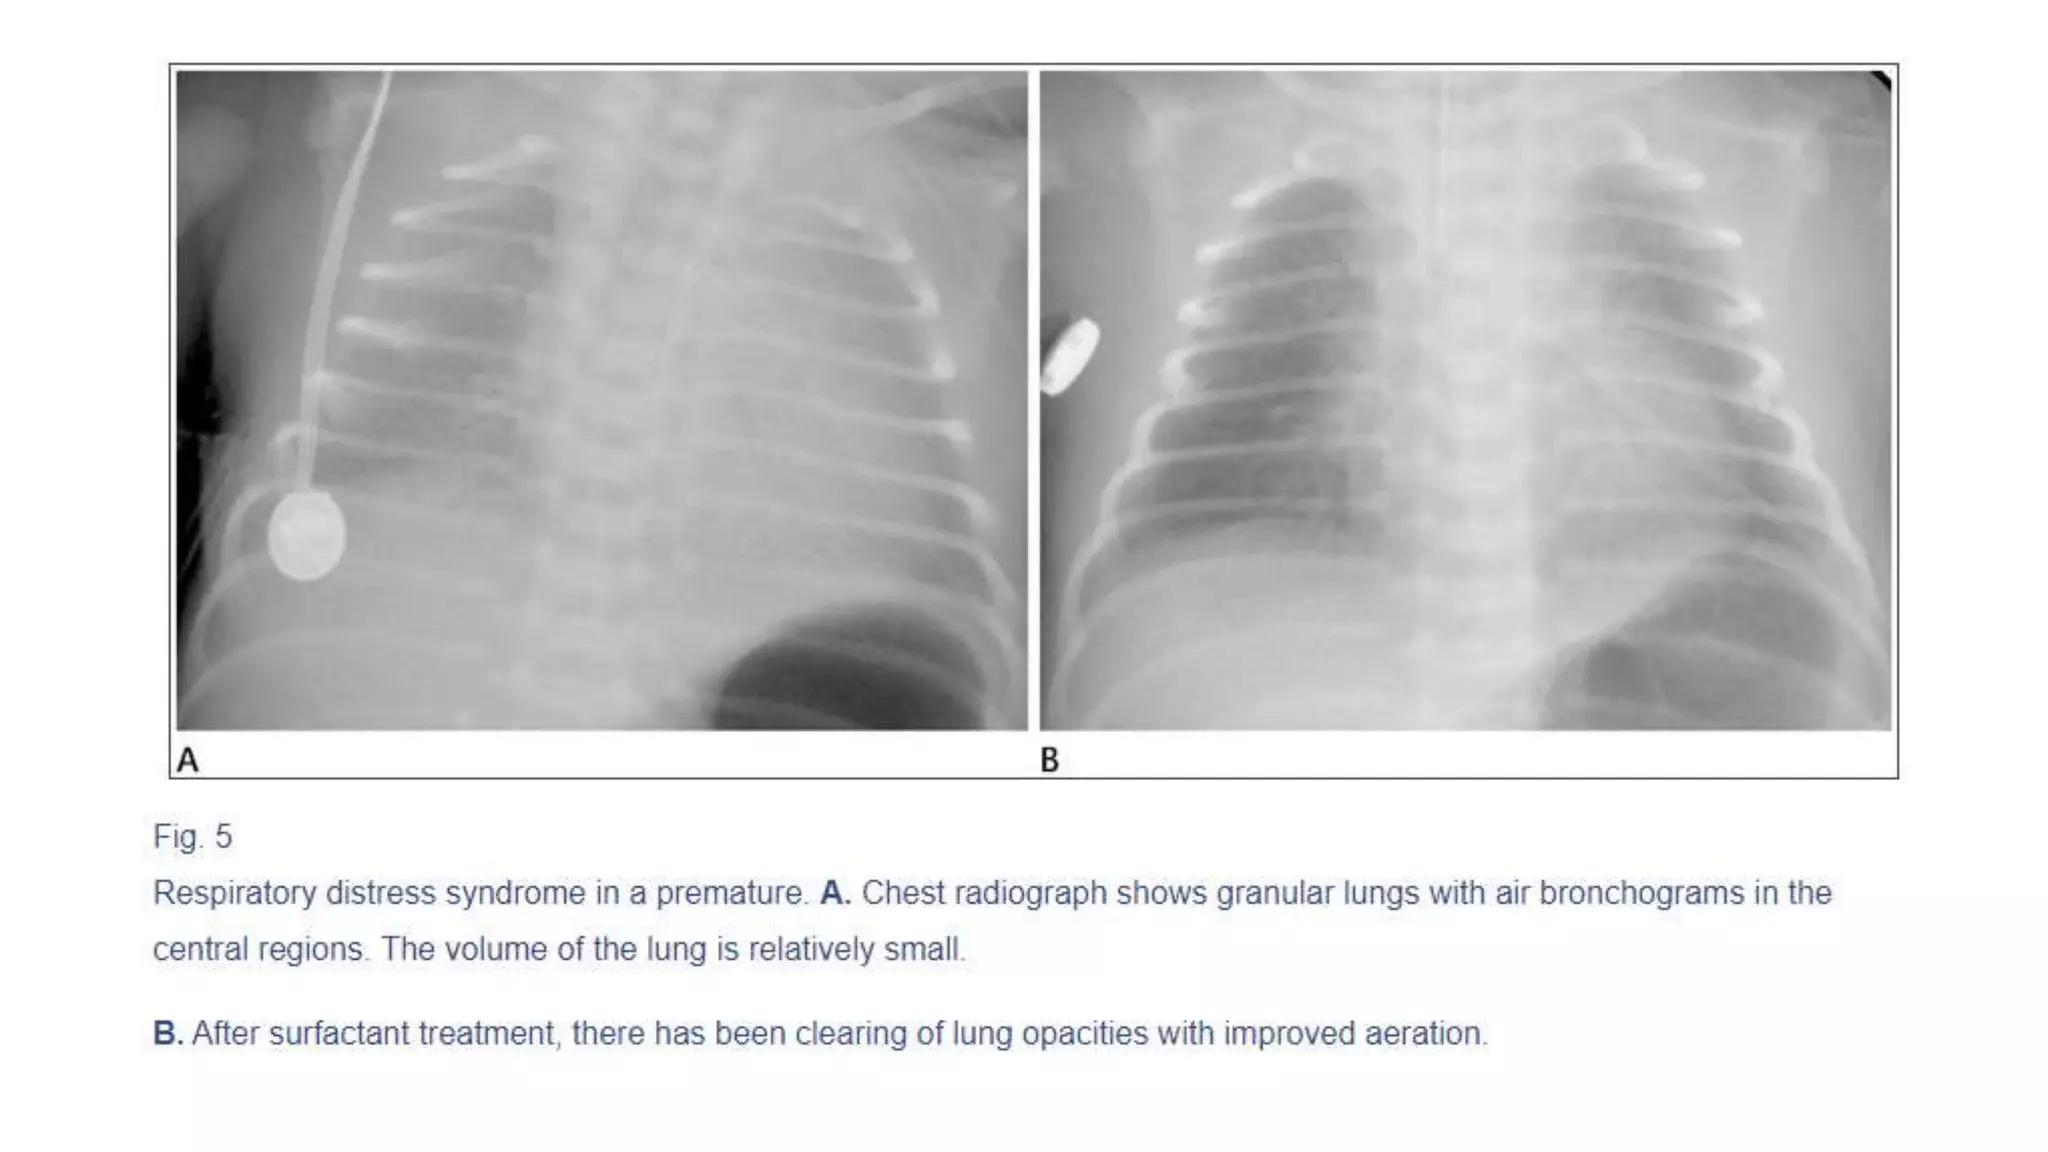

This document provides an overview of neonatal chest x-rays, including when they should and should not be performed, what a normal x-ray looks like, common positions of tubes and catheters, and common causes of respiratory distress in neonates. It discusses the appearance of a normal chest x-ray as well as conditions like respiratory distress syndrome, transient tachypnea of the newborn, meconium aspiration syndrome, and pneumonia. Surgical conditions like diaphragmatic hernia and esophageal atresia are also reviewed.